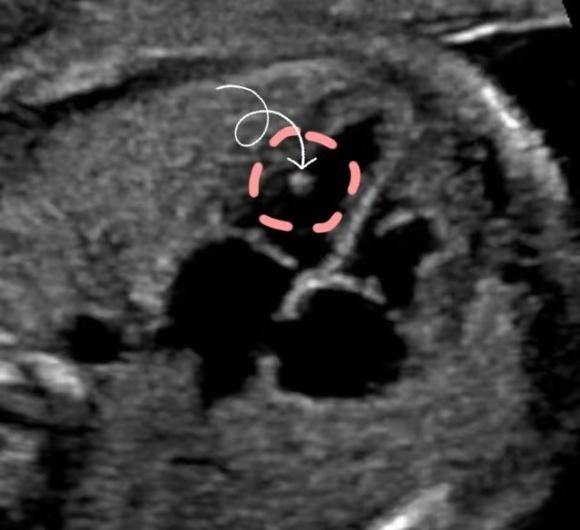

胎儿局灶性高回声灶是指位于乳头肌或腱索内的高回声灶,直径约1~6mm,其回声强度与骨骼接近,可为单发或多发,尤以左心室为多,或左右心室均有,发生率约为3.6%。是妊娠期常见的超声表现,可随着孕周的增加而逐渐减少和减弱,最迟在一年内消失。

(看,箭头标示的亮点是焦强回声)